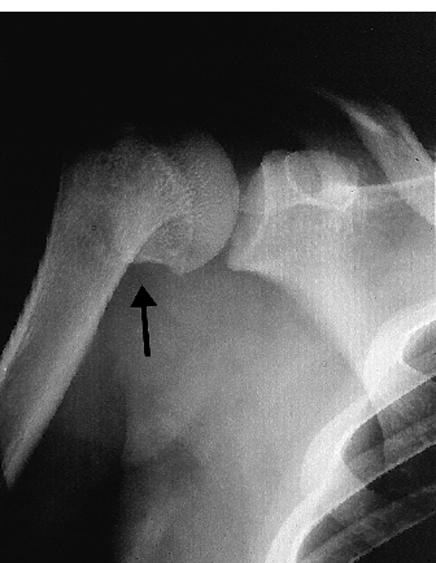

イカ レントゲン-もくじ 1 イカ・サバ注意! 新鮮な刺し身に危険な「アニサキス」とは 11 アニサキス症の症状;このレントゲン写真では、肩が押し下げられていることがわかるのではないでしょうか。 かゆい時や洗う方法は? また、気になるのは、お風呂の時、かゆい時や洗う方法ですよね。 首を保護するために、寝る時は高い枕を使用して、横を向いて眠るそう

スポーツ障害 野球肩 水泳肩 とは 医療総合qlife

変形性肩関節症 へんけいせいかたかんせつしょう 弁護士による交通事故相談 弁護士法人前島綜合法律事務所

主な疾患 スポーツ整形外科 半月板 前十字靭帯 肩 腰 足 肘の治療